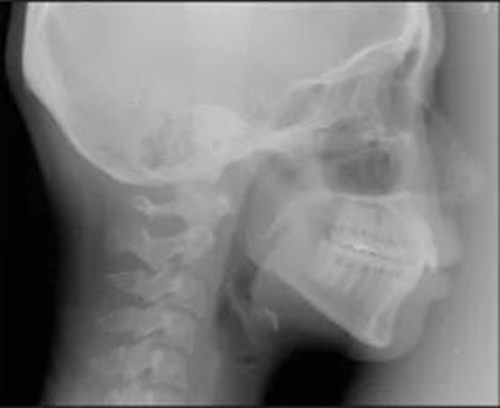

頭側(cè)分析提示為骨性安氏II類(ANB,8.4°;Wits,3.6mm),高角(SN-MP,44.9°),上頜切牙略舌傾(U1-SN,96.2°),下頜切牙略舌傾(IMPA,88。3°)(圖2;表)

治療后頭側(cè)數(shù)據(jù)提示:無明顯骨性變化(上頜SNA82.1°,下頜SNB74.9°),上頜前牙得到內(nèi)收,略舌傾,頦部前后位置無明顯改變,仍未凸面型(圖8,表)。將治療前后圖像重疊后結(jié)果如(圖8及圖9),24月后隨訪結(jié)果見圖10.